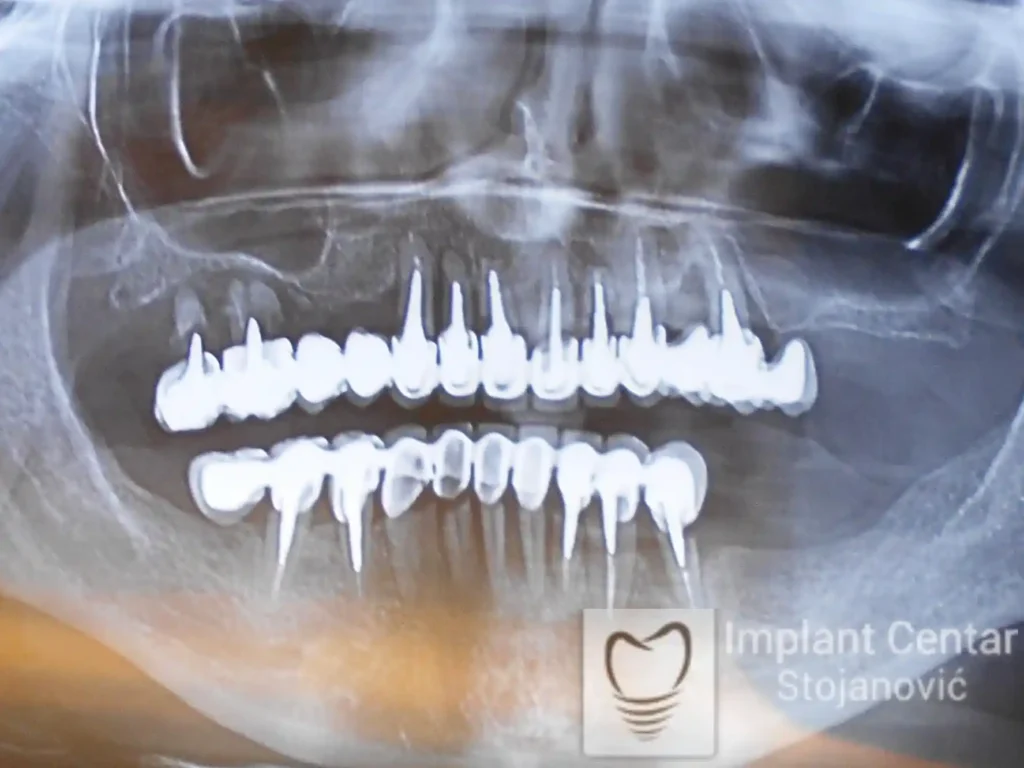

Na slici 1. i slici 2. prikazan je izgled pacijenta pre početka terapije – klinički i rendgenološki.

Nakon vađenja zuba, ugrađeni su implantati. Na slici 3 prikazan je ortopan snimak sa ugrđenim implantatima. Tokom perioda osteointegracije, pacijent je bio zbrinut fiksnim privremenim krunicama na implantatima, koje su izrađene samo dva dana nakon hirurške intervencije.